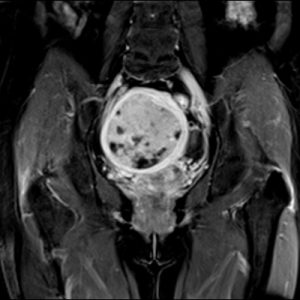

3. Ứng dụng

-

Chụp sọ não và cột sống

Chụp mạch máu (MR Angiography)

Khớp vận động (knee, shoulder, wrist)

Chẩn đoán ung thư (vú, bụng)

Chẩn đoán thần kinh, cơ xương khớp, chấn thương thể thao

Ứng dụng quét nhanh vùng bụng trong nhịp thở ngắn